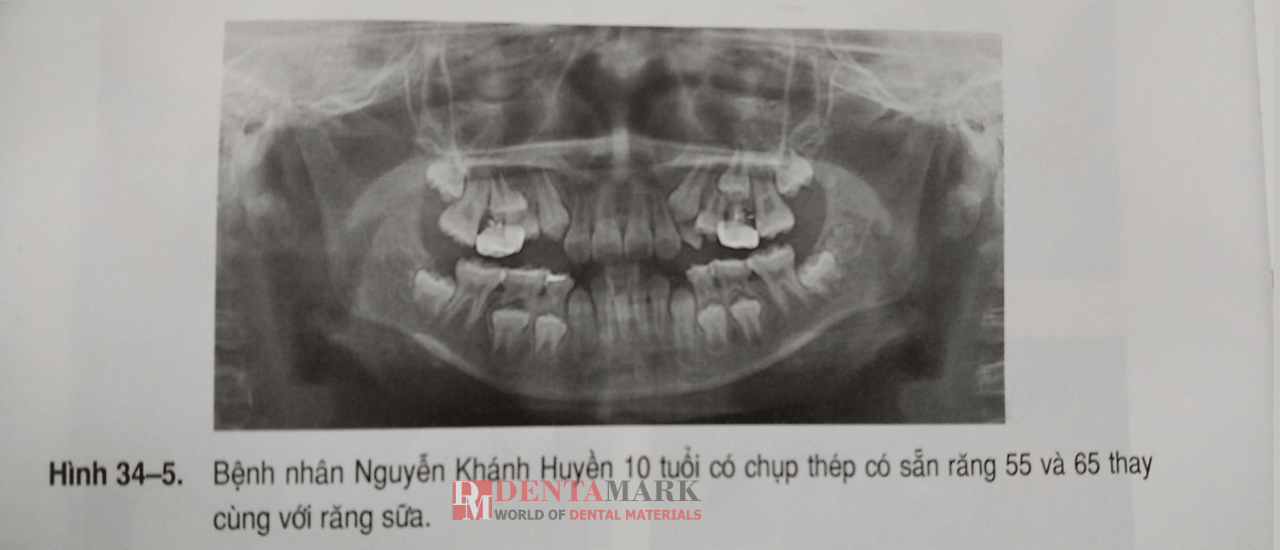

+ Chụp răng sẽ rụng cùng với răng sữa trước khi răng vĩnh viễn thay thế mọc.